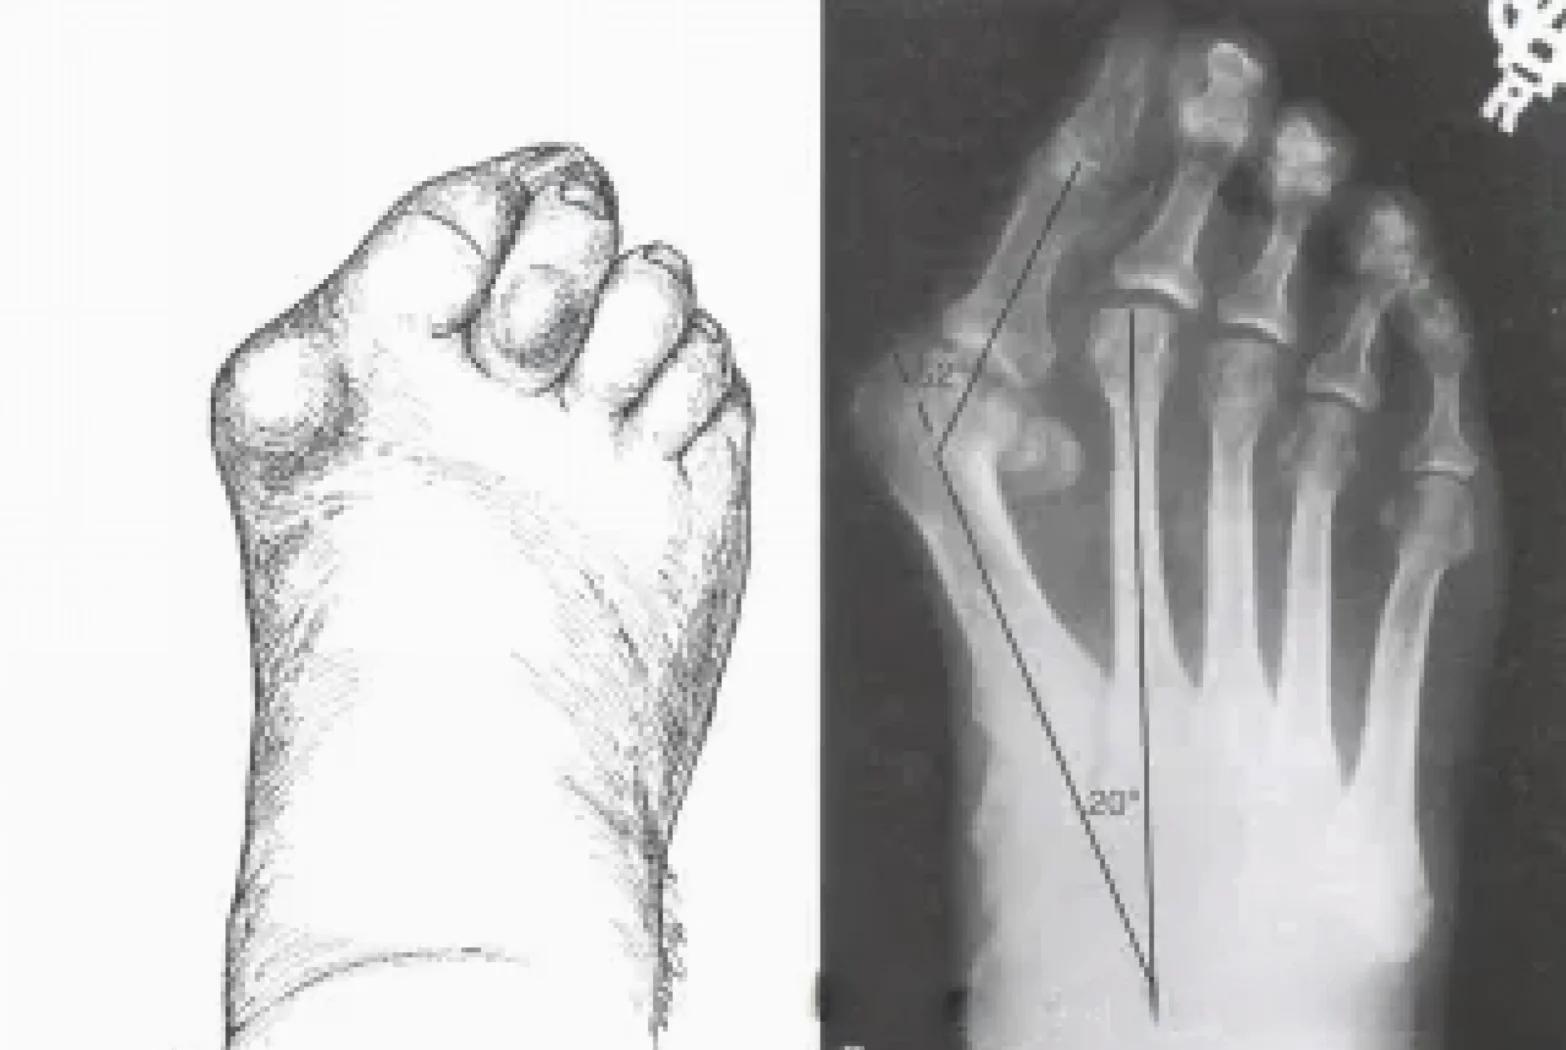

拇趾外翻畸形拇外翻畸形是指拇趾在第一跖趾关节处向外侧偏斜移位,外翻角度大于正常的15度,可以挤压第二足趾同时,第二跖骨和第二跖骨的角度也会加大疼痛具有拇外翻的患者不一定都有疼痛,而且畸形也与疼痛不成正比但拇跖骨头内侧隆起后压迫和摩擦会引起急性拇囊炎,导致疼痛此外,拇跖趾关。

拇外翻俗称大脚骨,是一种足部畸形,主要表现为足拇趾斜向外侧,第一跖骨内翻,多伴有拇囊炎疼痛等症状以下是关于拇外翻的详细解释主要特征足拇趾斜向外侧,第一跖骨内翻,第一二跖骨间夹角增大,跖拇关节轻度半脱位第一跖骨头在足内侧形成一骨赘,因长期受鞋帮的摩擦,局部皮肤增厚,严重时。